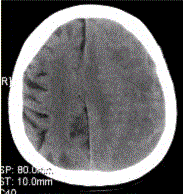

患者男,70岁。突发昏迷。头CT显示如下图。可能的诊断为A.硬膜下血肿B.正常C.硬膜外血肿D.脑挫裂伤E.脑脓肿F.脑炎

问题 患者男,70岁。突发昏迷。头CT显示如下图。 可能的诊断为

选项 A.硬膜下血肿 B.正常 C.硬膜外血肿 D.脑挫裂伤 E.脑脓肿 F.脑炎

答案 A